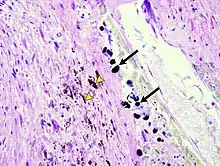

Micrograph of the spleen showing darkly stained, spheroid Gamna-Gandy bodies (arrows) outside the vessel wall at the center. Also shown is diffusely scattered, brown, granular hemosiderin pigment (arrowheads), indicating previous hemorrhage (hematoxylin & eosin staining, 40x magnification).

Gandy–Gamna nodules or Gandy-Gamna bodies, sometimes known as Gamna-Gandy bodies or Gamna-Gandy nodules, are small yellow-brown, brown, or rust-colored foci found in the spleen in patients with splenomegaly due to portal hypertension,[1] as well as sickle cell disease. They consist of fibrous tissue with haemosiderin and calcium deposits, and probably form due to scarring at sites of small perivascular haemorrhages.[2] They are visible on MRI scanning due to the presence of haemosiderin.[3]